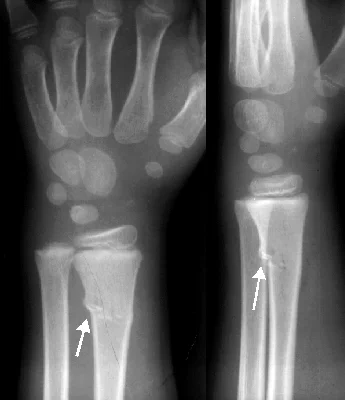

Stress Fractures

- Bone reacts to repeated loading, may become fatigued & a crack develops

- Fatigue fractures

- Abnormal stress or torque on a bone that has normal elastic resistance

- Examples:

- military recruits, athletes, ballet dancers

- Insufficiency fractures

- Normal muscular activity stresses a bone that is deficient in mineral or elastic resistance

Stress Fracture Details

- Usually Transvers

- 2nd metatarsal

- Tibia

- Fibula

- In osteopenia, osteomalacia

- Neck of femur

- Ribs

- Neck of humerus

- Scapula